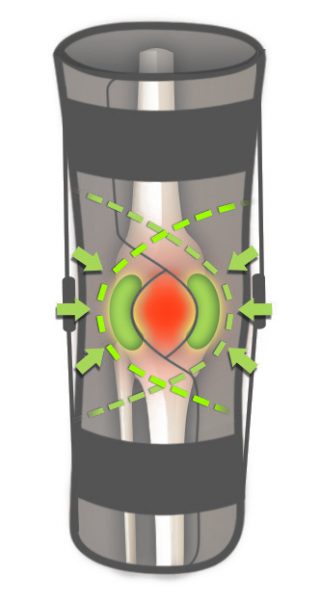

Każda orteza z serii IB jest wyposażona w dwie wyprofilowane peloty które wzmacniają i stabilizują rzepkę.

Każda orteza z serii IB jest wyposażona w dwie wyprofilowane peloty które wzmacniają i stabilizują rzepkę.